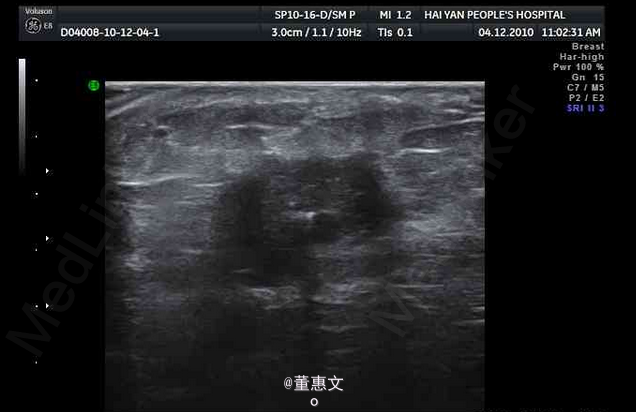

女,50岁,因3月前无意中发现右侧乳腺外下象限肿块前来就诊

无疼痛及皮肤破溃,活动度差,五畏寒发热。无胸痛及其他不适。 辅查超声

右乳腺癌 处理:手术配合放疗化疗